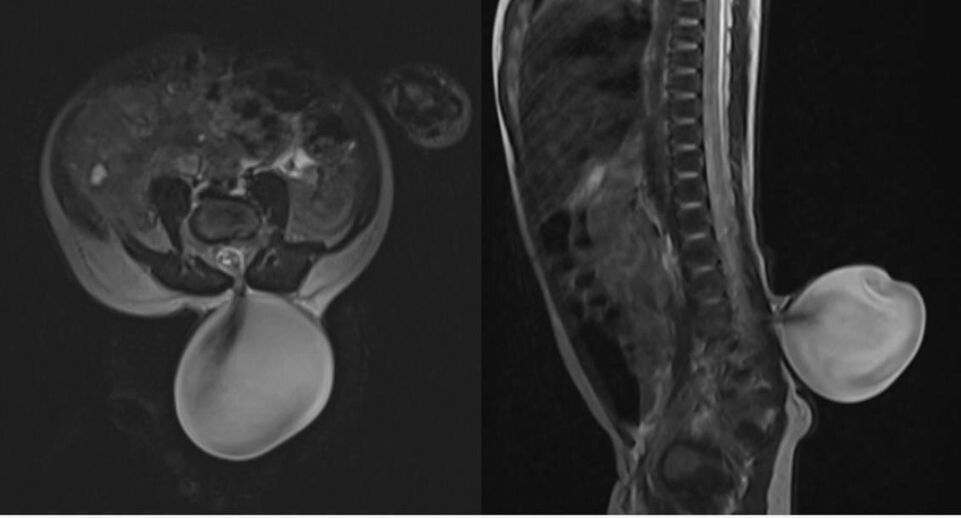

В Детском клиническом центре имени Л. М. Рошаля спасли новорожденного ребенка с редкой грыжей спинного мозга. Юному пациенту провели магнитно-резонансную томографию, которая подтвердила врожденный порок развития позвоночника — менингомиелоцеле.

Патология способна привести к значительному ослаблению мышц ног. Специалисты после обследования ребенка приняли решение о проведении операции.

«Сперва мы убедились, что спинной мозг зафиксирован к куполу грыжи. После аккуратно отделили спинной мозг от грыжевого мешка и восстановили нормальную анатомию позвоночного канала. Операция длилась два часа и прошла успешно, без осложнений», — пояснил заведующий отделением нейрохирургии Аслан Текоев.